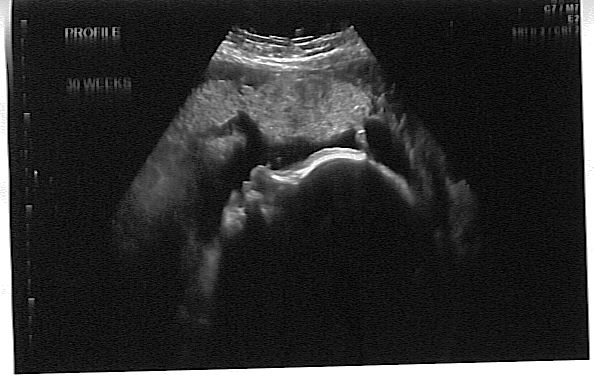

profile. The fuzzy line on the top of his head is hair!

I scanned it at this angle so maybe you could tell better what things were. You can see his forehead, right eye (closed), his nose is the darker smudge in the middle, and the darker lines near the bottom are his lips. Don't know if you can tell this or not but his cord was in the way so that's why you can't see his left eye or that part of his face. Doctor's appointment went fine today. His heartrate was in the 130s. My blood pressure was 110/63. I've gained 14.8 pounds total. She referred me to a derm. to have a mole removed as it has gotten much larger and is changing in color and texture. They are to call me when the appointment gets scheduled. We are signed up for birthing classes next month. I got my flu shot today too. They said they had the one there that did not have perservatives in it, and acted like they would rather I get it there than the one they might be offering at work. So I went ahead and got it today while I was there. Waited 20 minutes after I got it done to make sure I didn't have any problems. They didn't say anything about my urine, so I guess it was all fine. She said my belly was measuring around what it should be.

When I got the scan at work yesterday, they said he's weighing 3 pounds 13 oz and is at the 53%. So sounds like it's all good as far as I know.